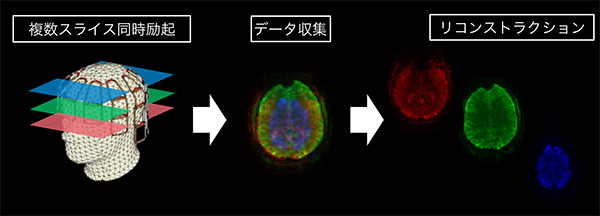

HyperBand(ハイパーバンド)

マルチバンドRF励起技術をDWI/DTI撮像に応用し,複数スライスを同時に励起・データ収集することで撮像を高速化するアプリケーションです。同じTRでより多くのスライス数を収集,もしくはTRの短縮により,従来より多くのMPG軸を印加して撮像することが可能となります。